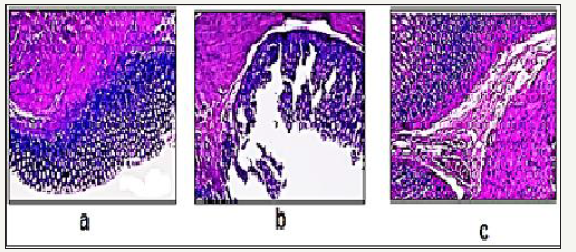

Figure 4: Representative images showing histological observations in rat gastric tissues after administration of the drug

4a: Control

4b: Uncoated

4c: Coated dexibuprofen.

Histolopathological examination: The histopathological pattern of the mucosal specimens was studied by examining the histology of the treated and control samples. Effect of both uncoated as well as coated dexibuprofen on stomach tissue histopathology is presented in Figure 4. Histopathological examination of Hx & E stained stomach sections of control rats (n=6), revealed that all the six animals showed completely normal gastric mucosa with excess mucous layer (Figure 4a). In uncoated dexibuprofen administered rats (n=6), histopathological examination revealed that all the six animals showed pronounced necrotic gastric mucosa with sever dilated congested blood vessels in the lamina properia with severe edema infiltrated by inflammatory cells (neutrophil infiltration), also superficial mucosal layer showed marked congestion, necrosis (Figure 4b). In case of dexibuprofen coated with pectin-rutin mixture administered rats (n=6), histopathological examination revealed that stomach tissue of animals showed near normal gastric mucosa (Figure 4c).